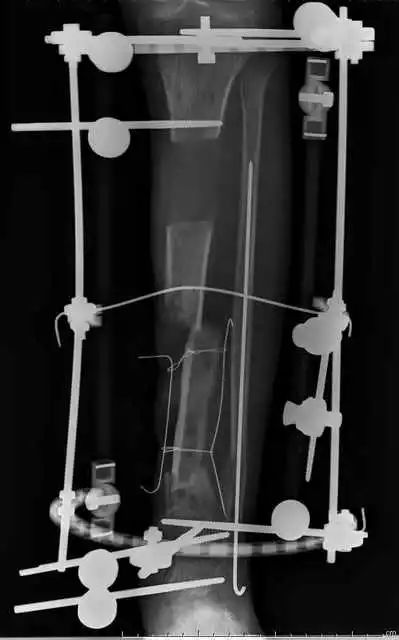

(网友提供)最后的病例是伤后40天由外地转来。开放骨折外固定架固定,骨坏死外露,用连珠和双氧水冲洗。入院时还存在足下垂,腓神经损伤、胫后动脉损伤。

Tips

• 接收该患者后第一次手术  清除病灶去除死骨27cm

• 抗生素骨水泥填塞。远端整块水泥包裹外露骨质,近端连珠以便骨搬移

• 钢丝克氏针张力牵拉皮肤,缩小创面

• 5天后下地部分负重走路

• 联合骨牵引纠正足下垂,5天后足下垂纠正后去除跟骨骨牵引针,保留胫跖骨牵引维持足于功能位。

• 而后行骨搬移、半开放植骨(如下)